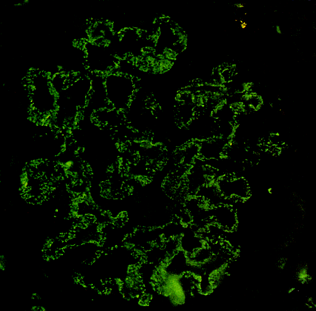

免疫荧光: 可见免疫球蛋白IgG和补体C3呈粗颗粒状沉积于肾小球毛细血管壁。

电镜下: 除证实肾小球内增生的细胞主要是系膜细胞和内皮细胞,渗出的细胞是中性粒细胞等外,可见基底膜外侧或上皮下有高密度、大团块电子致密物沉积。沉积物从基底膜向外侧形成驼峰状突起(hump)。